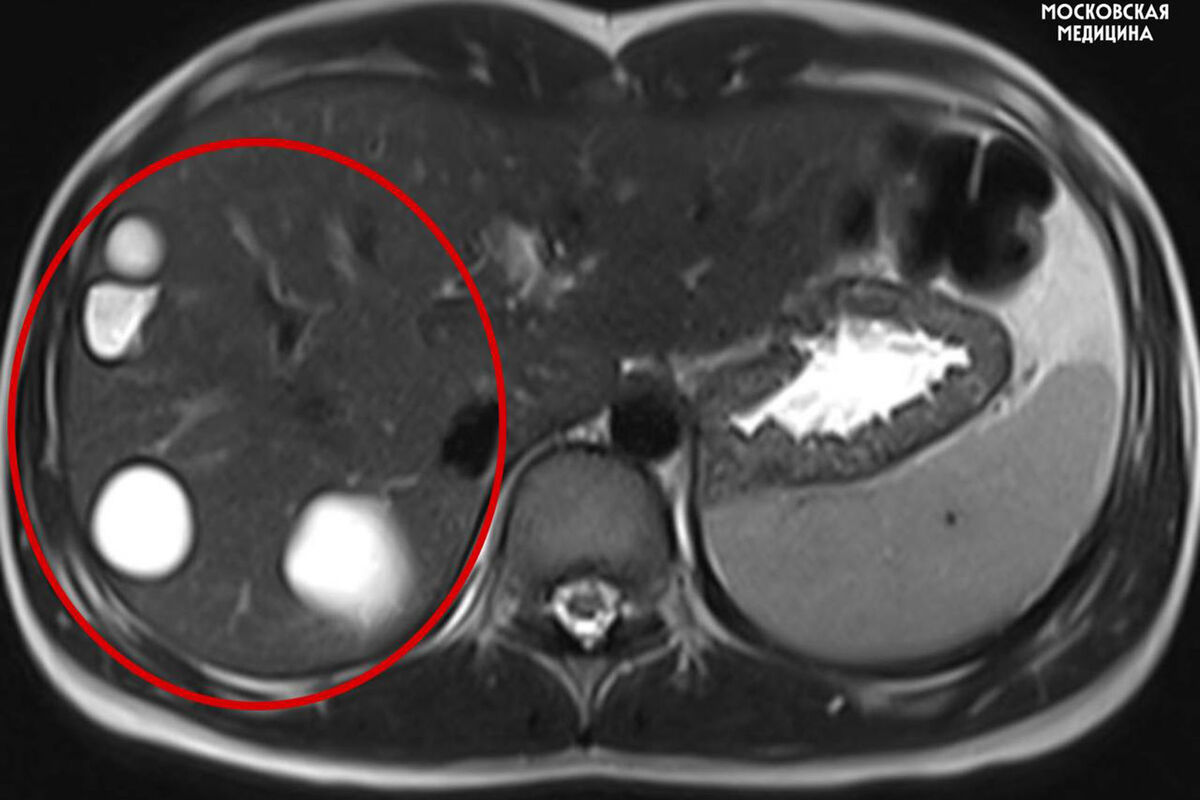

Врачи больницы имени Сперанского спасли 14-летнюю девочку с множеством паразитарных кист в печени. Об этом сообщили в пресс-службе столичного департамента здравоохранения.

Кисты медики обнаружили случайно во время планового обследования. После этого ребенка направили на операцию.

«Как правило, эхинококкоз выявляется на поздних стадиях и чаще всего случайно. В большинстве случаев симптомы заболевания неспецифичны: боль, кашель, незначительная температура и ощущение тяжести в животе, аллергические реакции», — пояснил заведующий хирургическим отделением №1, профессор Игорь Хворостов.

Во время вмешательства специалисты удалили пять кист с использованием лапароскопии. Через пять дней после операции пациентку выписали домой.